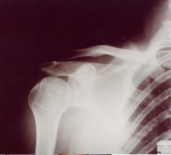

Foto 2

Foto 5